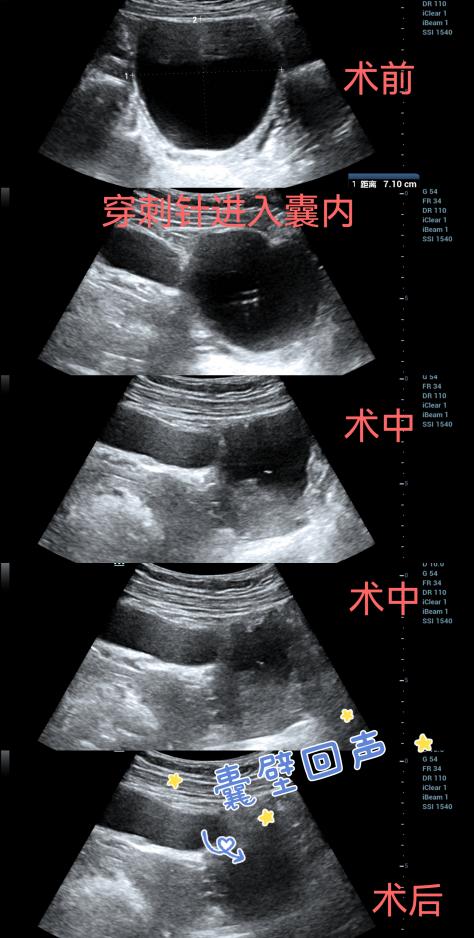

36岁的徐女士是一名医务工作者,发现卵巢囊肿多年,每年定期复查,深受其困扰,近期例行复查时发现卵巢囊肿大小为7.1cm×6.3cm。因囊肿体积、张力较大,会存在蒂扭转、破裂等风险,超声科主任刘晓晖建议徐女士行超声引导下囊肿抽液并硬化治疗术。经过与徐女士协商,决定行该项技术。整个过程从准备到囊液抽完,仅耗时15分钟,抽出170ml淡黄色清亮液体,超声声像图囊肿也由最初的鸡蛋大小仅剩囊壁回声,徐女士全程无任何不适,术后经观察后自行离开。

超声引导下囊肿穿刺治疗是在超声实时监测下,通过局部麻醉后将穿刺针刺入囊肿中心,先抽尽囊液,随后向囊内注入无水酒精等硬化剂凝固囊壁。超声介入囊肿穿刺治疗具有全程可视、安全精准、价格低廉、并发症轻微、创伤微小、恢复快等特点,临床治愈率达90%以上。且对于复发的囊肿可以再次进行治疗,已成为各种囊肿首选的微创治疗方法。